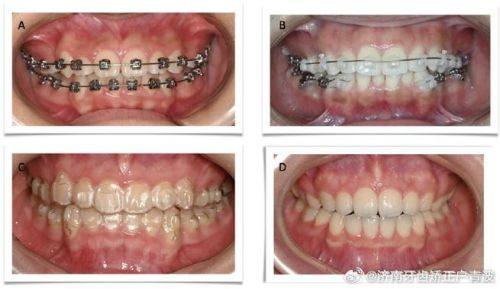

牙齿矫正:拥有经验多的正畸医生团队,结合数字化诊疗技术,可开展金属托槽矫正、隐形矫正等多种矫正方式,为不同牙齿畸形患者制定专属矫正方案,矫正过程中医生会全程跟踪指导,患者反馈就诊体验佳,矫正成效稳定。